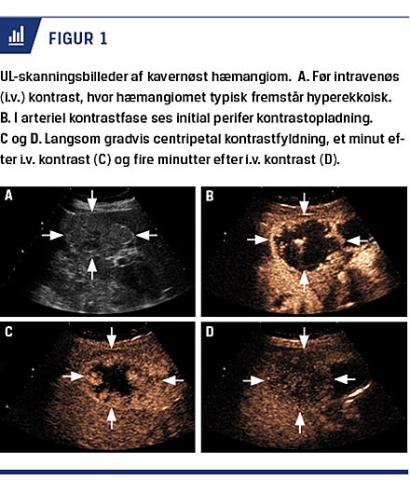

Billeddiagnostik

Kavernøst hæmangiom (KH) fremstår på UL-skanninger velafgrænset og ekkorig. Ved CT er KH isodens til blod. På MR-skanning på T1-vægtede sekvenser er KH velafgrænset og isointens til blod og på T2-vægt-

ede sekvenser hyperintens. Hvis der anvendes intravenøs (i.v.) kontrast ses der i arteriel kontrastfase på

både UL-skanning, CT og MR-skanning initial perifer kontrastopladning efterfulgt af langsom centripetal fyldning (Figur 1) [9]. På CT er KH kendetegnet ved isodensitet til blod i alle kontrastfaser. 16% af hæmangiomerne er flash filling/kapillære hæmangiomer (FFH) [10]. FFH er oftest < 20 mm og adskiller sig fra KH ved momentan kontrastopladning (flash filling) i arteriel kontrastfase på alle billedmodaliteter. Uden i.v. kontrast kan FFH ikke skelnes fra KH, og fælles for begge hæmangiomer er, at kontrastopladning persisterer uden udvaskning i senere kontrastfaser i modsætning til ved hepatocellulært karcinom (HCC) og hypervaskulære metastaser [6].